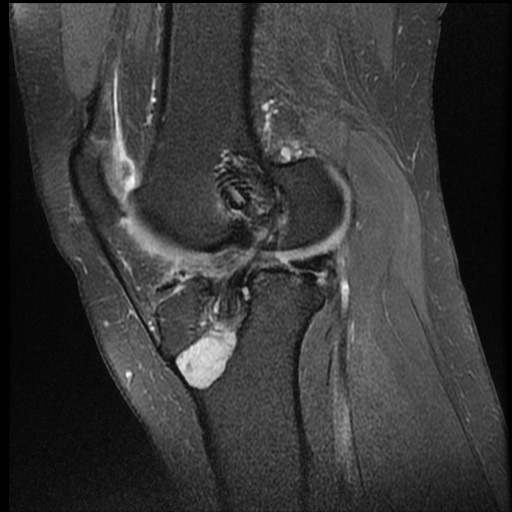

Osteosarcoma

image